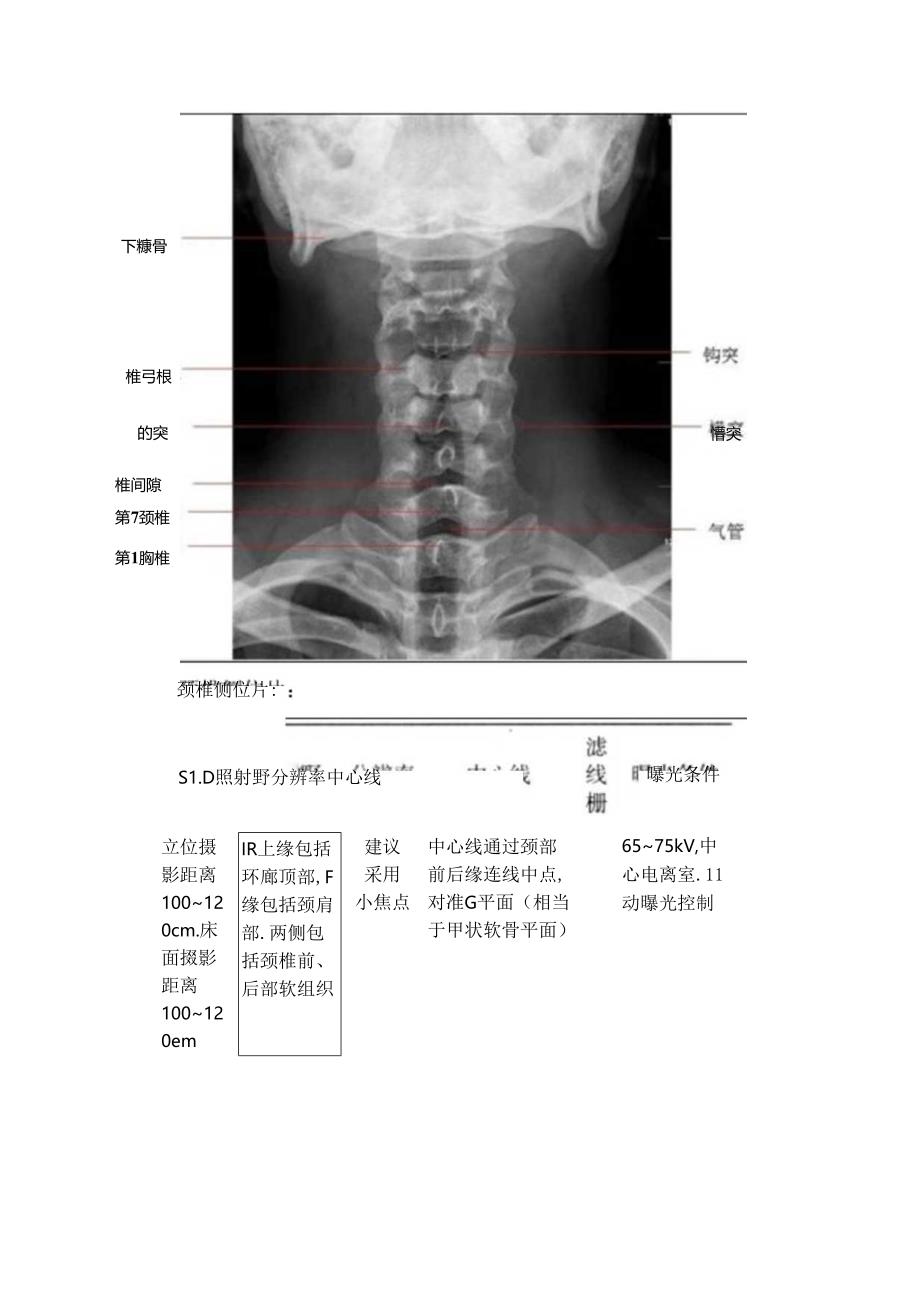

1、临床颈椎X线摄影距离摄影思考颈椎病颈椎病是由于椎间盘变性、椎间小关节软骨退行性改变、坏死,而引起椎体周围骨质增生,椎旁和椎管内韧带增生、肥厚、骨化,导致椎间孔变形、椎管变窄,刺激或压迫颈椎脊神经根、交感神经、椎动脉、脊髓而产生一系列临床症状。根据不同解剖部位的压迫程度,临床上将颈椎病分为:脊神经根型、交感神经型、椎动脉型、行髓型和混合型,而临床上最多见的是行神经根型。摄影技术颈椎正位片:SID分辨率送中心线线ffi曝光条件才位期IIKt缘齐建议站立耐后H1.65COkV.影距离平外耳孔.采用位.XttffA中心电力100-I2*m床而掇影距离100im下缘包括小焦点T1.两侧包括颜都软姐职头端

2、憾斜I5.H的IiX线适应知他前凸度,层可同行通过椎间W中心线时清正中矢状线G囱(相当JSRR角水平)仲卧正位.中心线向头战帧科10。(W)卧位时,前凸度可能降低.“平If1.化可适当成小向度)疑椎优情况V.单椎弓度变1.中心线向头端帧斜s.wsrtItG(甲状软什水平)室.自动期光控制下糠骨椎弓根的突懵突颈椎侧位片:曝光条件椎间隙第7颈椎第1胸椎S1.D照射野分辨率中心线立位摄影距离100120cm.床面掇影距离100120emIR上缘包括环廊顶部,F缘包括颈肩部.两侧包括颈椎前、后部软组织建议采用小焦点中心线通过颈部前后缘连线中点,对准G平面(相当于甲状软骨平面)6575kV,中心电离室.